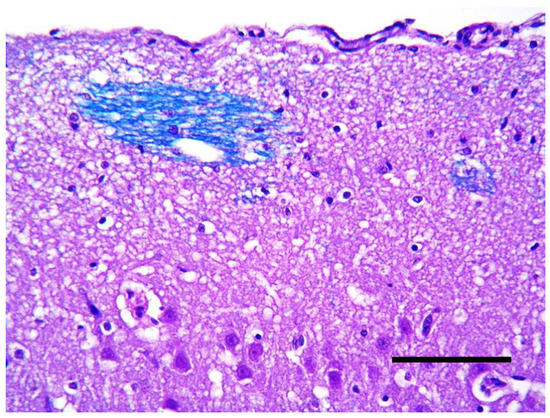

Gangliogliomas are extremely rare tumors of the nervous system composed of neoplastic glial and neuronal cells. The aim of the present paper is to describe the clinical presentation, magnetic resonance imaging (MRI) findings and histopathological and immunophenotypical characteristics of a cerebral cortex ganglioglioma [...] Read more.

Gangliogliomas are extremely rare tumors of the nervous system composed of neoplastic glial and neuronal cells. The aim of the present paper is to describe the clinical presentation, magnetic resonance imaging (MRI) findings and histopathological and immunophenotypical characteristics of a cerebral cortex ganglioglioma in a 7-year-old Border Collie. The dog presented an acute onset of tonic-clonic epileptic seizures. MRI revealed a well-defined large intra-axial mass located on the left forebrain, mainly affecting the frontal cortex. Following humane euthanasia, the histopathological examination of the mass revealed a diffuse proliferation of neoplastic glial cells mixed with anomalous neuronal bodies. Immunohistochemical analyses confirmed the presence of two different populations of neoplastic cells. Most neoplastic glial cells were immunoreactive to glial fibrillary acidic protein (GFAP) and the other subset of neoplastic cells were positive to neuronal markers such as PGP 9.5, synaptophysin (SYN) and neuron-specific enolase (NSE), suggestive of neuronal cells. These findings confirmed the diagnosis of a cerebrocortical ganglioglioma. To the authors knowledge, this is the first description of a ganglioglioma of the cerebral cortex in a dog. Full article